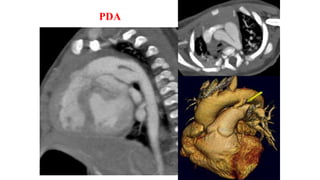

Patent ductus arteriosus. Volume render CT and Sagittal steady-state free

precession image of 32-year-old man shows patent ductus arteriosus

(straight arrow) connecting aortic isthmus with main pulmonary artery

(PA), with high-velocity jet (curved arrow) present throughout cardiac

PDA with jet flow from aorta to PA

Sagittal coronal

PDA CT ANGIO